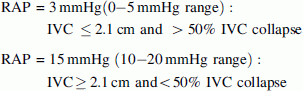

Initial ED bedside echocardiography was performed (see Video Clips S1, S2, S3, S4, and S5, available as supporting information in the online version of this paper). Examination of the heart with a low frequency array cardiac probe in the apical four-chamber view revealed right ventricular hypertrophy and a combined atrial septal defect (ASD) and ventricular septal defect (VSD) with no pericardial effusion (Fig. 1; Video Clip S1). A color Doppler subcostal view revealed a left-to-right shunt from the left ventricle to the right atrium (Fig. 2; Video Clip S2). Right ventricular outflow tract view (RVOT) evaluation of the aortic valve revealed a bicuspid aortic valve (Fig. 3; Video Clip S3). Parasternal short axis view at the level of the papillary muscles showed right ventricular pressure and volume overload with a D-shaped left ventricle present during both systole and diastole and a large dilated right ventricle (Fig. 4; Video Clip S4). Color Doppler evaluation of the tricuspid valve in the right ventricular inflow tract view (RVIT) revealed tricuspid regurgitation (Fig. 5; Video Clip S5). In addition, in the RVIT view (Fig. 6), continuous wave Doppler revealed tricuspid regurgitation with a 2.76 m/s regurgitant jet. Right ventricular systolic pressure (RVSP) was estimated elevated at 45.4 mmHg (greater than 25 mmHg is abnormal) from this tricuspid regurgitant jet velocity using the modified Bernoulli equation and combining this with an estimate of the right atrial pressure (RAP) [1]. Right ventricle systolic pressure (RVSP) = pressure gradient between the RV and RA = 4 × [tricuspid regurgitant Doppler jet velocity (meters/second)]2 + right atrial pressure (RAP) [1]. Right atrial pressure was estimated at 15 mmHg, as the patient had an inferior vena cava (IVC) diameter >2.1 cm and had less than 50% inspiratory collapse of the IVC in the subcostal view of the IVC going into the right atrium (Fig. 7) [1]. Using the modified Bernoulli equation and RAP estimation using IVC inspiratory collapse method recommended by the American Society of Echocardiography [1]:

RAP may be estimated with subcostal IVC measurement and IVC inspiratory collapse:

In our patient: